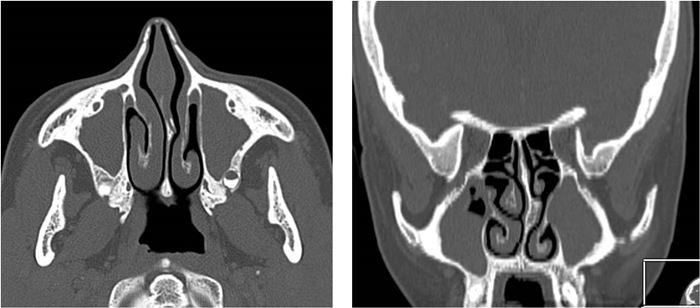

Diagnostyka obrazowa zatok staje się coraz bardziej istotna dla lekarzy dentystów, którzy posiadają w swoich gabinetach aparaty tomografii stożkowej (CBCT). W zależności od wielkości pola obrazowania w CBCT są widoczne fragmenty zatok szczękowych aż po całe zatoki szczękowe, a w badaniach o największym polu obrazowania wszystkie zatoki oboczne nosa, podobnie jak w badaniu medycznej tomografii komputerowej (TK). Z tego względu celem pracy jest przedstawienie najważniejszych zmian patologicznych zatok szczękowych, z którymi może się spotkać lekarz stomatolog, opisując badania tomografii stożkowej (CBCT).